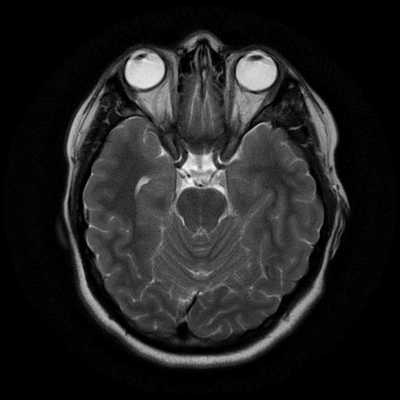

Исследование выполняется в нескольких режимах. Основные из них Т1 и Т2. Изображения, полученные в данных режимах, часто также называют Т1-взвешенными или Т2-взвешенными снимками. Изображения, показанные выше, сделаны в Т1-режиме.

Главное отличие этих режимов - в том, как на снимках отображается жидкость и воздух. В Т1 режиме ткани, содержащие большое количество воды, имеют более темную окраску, в то время как в Т2 режиме они яркие, светлые. Это легко понять, посмотрев на снимки выше - глазные яблоки визуализируются в виде светлых парных округлых образований с одной стороны яркие и светлые, с другой - темные. Следовательно, снимок справа сделан в Т1 режиме, снимок слева - в Т2. Также существует разница в том, как в этих режимах отображается серое вещество головного мозга. В Т2 режиме оно светлее, чем белое вещество.